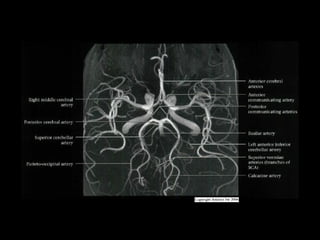

Gross Anatomy

• Anterior Circulation

- Intracranial Internal carotid artery and its

branches + ACoA, PCoA

• Posterior Circulation

- Basilar artery and its branches

Basilar Artery

•

Courses cephalad in prepontine cistern to terminal bifurcation

ventral to midbrain

- Gives off AICA, superior cerebellar arteries (SCAs), pontine,

midbrain perforating arteries

• Bifurcates into POSTERIOR CEREBRAL ARTERIES, each of

which has 4 segments

- Mesencephalic or pre communicating (P1) segment lies within

interpeduncular cistern, curves posterolaterally from BA to PCoA

junction

- Ambient (P2) segment extends from PCA-PCoA junction, curving

around cerebral peduncles just above tentorium, above oculomotor

nerve

- Quadrigeminal (P3) segment extends posteromedially from level

of quadrigeminal plate

- Cortical (P4) branches arise from distal PCA at or just before

reaching calcarine fissure

- Perforating branches arise from P1

• Vertebral arteries

- Intracranial (V4) segments enter dura near foramen magnum

- Give off anterior/posterior spinal arteries, perforating arteries

to medulla, PICA